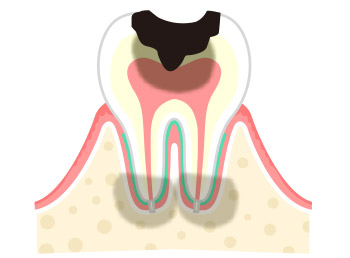

虫歯は、細菌が作る酸によって、歯が溶かされる病気です。細菌によって歯が溶かされることを「脱灰」と言い、溶かされた歯を修復する働きを「再石灰化」と言いますが、この「脱灰」と「再石灰化」のバランスが崩れることによって、虫歯が発生してしまいます。 最初は歯の表面(エナメル質)で生じた虫歯も、進行するにつれてどんどん歯の奥へと進行してしまいます。進行すると神経の治療(根管治療)が必要になり、重度になると抜歯が必要になってしまいます。

| 症状 | 虫歯の影響で痛みがでる |

|---|---|

| 治療法 | 神経を除去し土台を立てて被せ物をする |

| 症状 | 歯が溶け、膿が出る |

| 治療法 | 抜歯後、補綴治療を行う(ブリッジ・入れ歯など) |